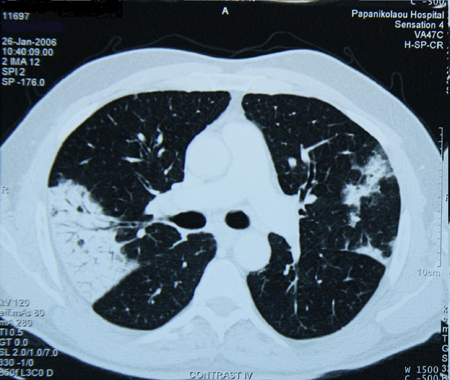

• High-resolution CT imaging of the chest to look for bronchiectasis (which does not always promote a productive cough), foreign body aspiration, pulmonary fibrosis, or other structural lung disease (which may not show well on chest x-ray). Chronic suppurative lung disease is diagnosed in patients with clinical symptoms of bronchiectasis but no radiographic evidence of bronchiectasis.[50] CT imaging may also indicate the presence of an aortic aneurysm or Zenker’s diverticulum. The diagnostic yield of the CT scan of the chest in a patient with chronic cough and normal chest x-ray is expected to be low.[3][Evidence C] There is no high-quality evidence to support the use of chest CT in the initial evaluation of patients presenting with chronic cough.[38]

[Figure caption and citation for the preceding image starts]: Chest CT with presence of signet ring on left in a patient with bronchiectasisFrom the personal collection of Dr S.M. Bhorade, University of Chicago Medical Center [Citation ends].com.bmj.content.model.assessment.Caption@769db40d[Figure caption and citation for the preceding image starts]: Chest CT with dilated and thickened airways and peripheral tree-in-bud pattern in a patient with bronchiectasisFrom the personal collection of Dr S.M. Bhorade, University of Chicago Medical Center; used with permission [Citation ends].com.bmj.content.model.assessment.Caption@5d8c3fb7[Figure caption and citation for the preceding image starts]: Chest CT showing idiopathic pulmonary fibrosisFrom the personal collection of Dr J.C. Munson, Center for Clinical Epidemiology and Biostatistics, University of Pennsylvania School of Medicine [Citation ends].com.bmj.content.model.assessment.Caption@43159570[Figure caption and citation for the preceding image starts]: Chest CT of a patient with amiodarone pulmonary toxicity, showing asymmetrical opacities with a peripheral distributionFrom the personal collection of Dr A. Pataka and Professor P. Argyropoulou, Aristotle University, Thessaloniki, Greece [Citation ends].com.bmj.content.model.assessment.Caption@33fbbbbd[Figure caption and citation for the preceding image starts]: CT of the chest with intravenous contrast material showing complete left lower lobe collapse with a radiopaque object within the left lower main bronchus surrounded by a halo of airBMJ Case Reports 2008 (doi:10.1136/bcr.06.2008.0013). Copyright 2008 BMJ Publishing Group Ltd [Citation ends].com.bmj.content.model.assessment.Caption@72dca222[Figure caption and citation for the preceding image starts]: Bronchoscopy image showing a loquat seed completely occluding the bronchus intermediusFrom the personal collection of Dr S. Murgu and Dr H. Colt, University of California at Irvine Medical Center [Citation ends].com.bmj.content.model.assessment.Caption@18215d6d